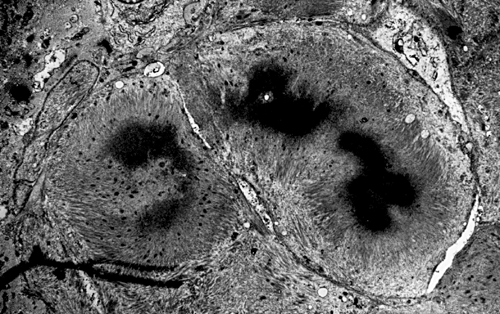

On hematoxylin-eosin stained sections, there is an increased variation of fiber diameter with many atrophic fibers intermingled with fibers of normal caliber. There is no evidence of fiber grouping or perifascicular atrophy. No inflammatory cells are present. There is also mild interstitial fibrosis (Panel A). On higher magnification, many fibers have a round concentric structure (Panel B). Irregular, centrally located depositions are also identified on modified Gomori's trichrome. The concentric nature, however, is not as obvious as in the hematoxin-eosin stained sections (Panel C). Type I and II fibers are not clearly separated in the ATPase preparation at pH 9.4. This is a common situation in chronically ill muscle (Panel D). The type I fibers are unusually dark. There is an increase in the proportion of type I fibers. The atrophic fibers are usually type II fibers. The concentric lesions are found predominantly in type I fibers (Panel E). There is an increase in PAS staining which is consistent with increased glycogen storage (Panel F). No increase in lipid content is demonstrated by oil red O (Panel G). On NADH-TR reaction, the concentric structures appear to have a clear central core that is devoid of enzymatic activity, a rim with intense enzymatic activity and a surround zone with relatively normal reactivity. These features are classic for target fibers (Panel H and I). No deficiency of laminin-2 (merosin) (Panel J) or dystrophin (Panel K) is demonstrated by immunohistochemistry. The central lesions are also immunoreactive for both laminin-2 and dystrophin. Immunohistochemistry for desmin demonstrate a core of strong immunoreactivity and also strong reaction in the sarcoplasmic membrane (Panel L and M). The target structures are also well demonstrated on semithin sections (Panel N). On electron microscopy, z-disc streaming is a common finding and they are often admixed with a substantial amount of dense granular electron dense substance (Panel O and P). There are also numerous cytoplasmic bodies characterized by radiating intermediate filaments (spheroid bodies) (Panel Q and R).

The two major pathologic findings are inclusion bodies and granulofilamentous material. Type I fibers are predominantly affected. Inclusions are eosinophilic on hematoxylin-eosin stain and bluish on modified Gomori’s trichrome stain. These inclusions are often negative for oxidative enzymes. A strong reactivity for desmin can be demonstrated by immunohistochemistry. The abnormal accumulation can occur as cytoplasmic inclusions, subsarcolemmal inclusions, spheroid bodies (10-20 mm oval or spherical inclusions), and patches or “hyaline structures”. In some cases, there is Z-disc streaming but no masses are demonstrated by trichrome stain. Numerous negative areas may be demonstrated by oxidative enzyme reactions. An accentuated intermyofibrillar network is seen by antidesmin antibody staining. Under the electron microscope, spheroid bodies appear as cytoplasmic bodies with a dense, granular core surrounded by fine filaments in a coronary arrangement. Although they are conspicuous on light microscopy, they may not be as distinctive at the ultrastructural level.

Granulofilamentous materials, also known as dappled dense structures” are dense anatomosing and trabeculated granular material that is about 100 nm in diameter is accumulated in between myofibrils or under the sarcolemma. The Z-disc streaming may appear contiguous to the granular deposits. They also appear as “non-hyaline” structure on immunofluroesent microscopy.Cytoplasmic bodies characterized by radiating intermediate filaments (spheroid bodies) are also common.